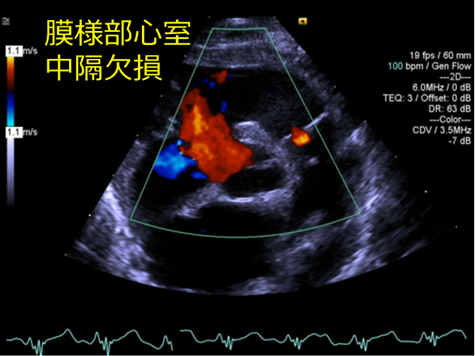

心室中隔欠損(VSD)とは

心室中隔に先天的に欠損がある状態のこと。

欠損孔を通して主に左室から右室への短絡があり、肺血流量が増え、心臓と肺への負担が増えます。